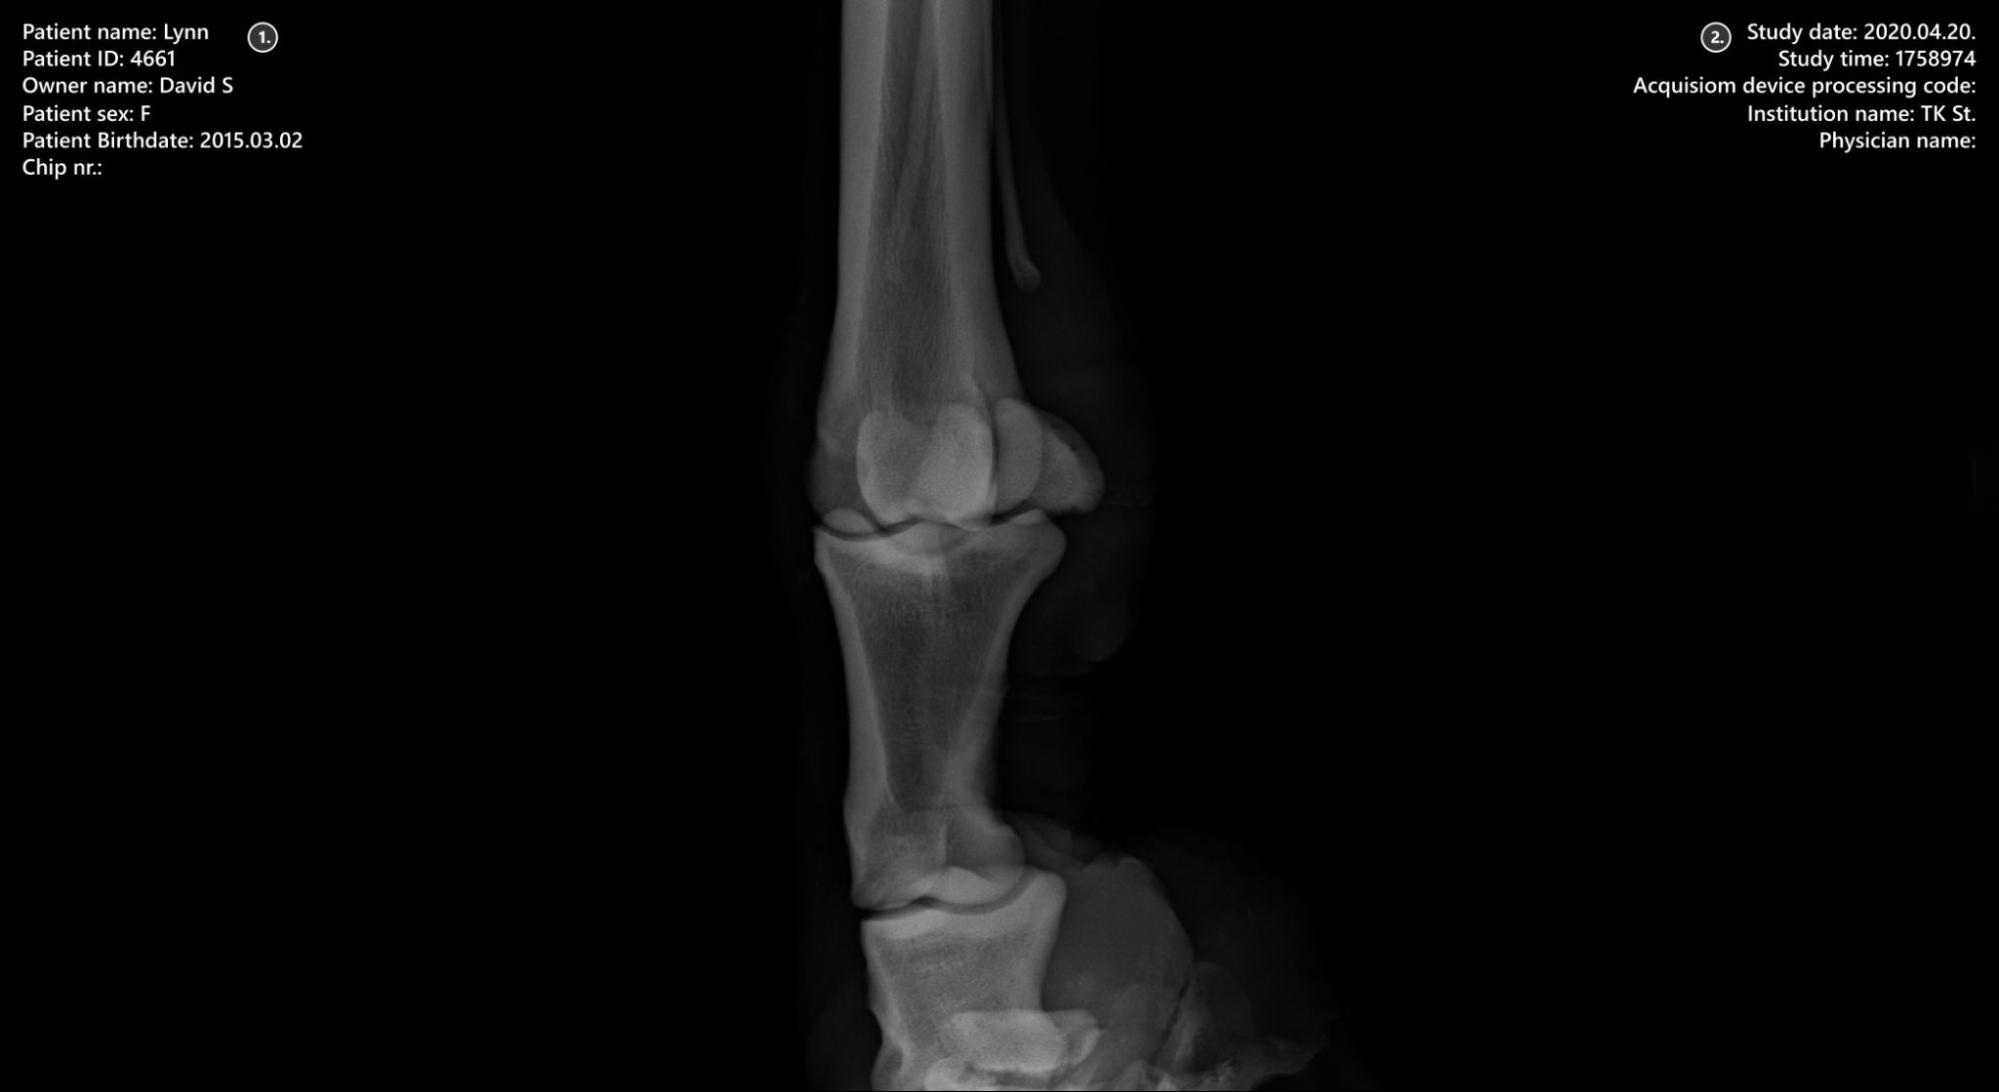

Viewer Area

../_images/image285.jpg

1. Patient information

2. Study information